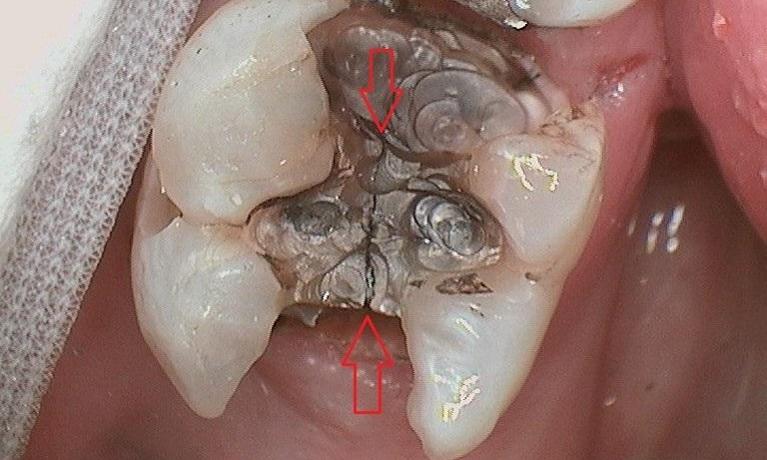

Here is a patient’s molar with a large silver filling with multiple cracks throughout. The patient was beginning to have sensitivity when chewing food. We suspected there was a crack in the tooth. Because the filling was showing such wear and because the tooth was becoming sensitive, we recommended a crown (cap). When we removed the old silver filling, we noticed the crack (noted by the red arrows). Given enough time this crack would have propagated (similar to a crack in a windshield) and the tooth would have broken in half down to the nerve. After placing the tooth-colored ...